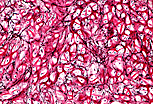

弹性软骨组织 的细胞外基质中,除II型胶原纤维外,还含有大量弹性纤维(本图中经品红-多聚甲醛染色呈红紫色)。这些交织成网的弹性纤维在每个软骨细胞周围形成致密网络,赋予该软骨组织极强的变形能力。 |